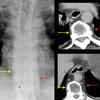

paraspinal interface

Date: 04/02/2014

Views: 3902